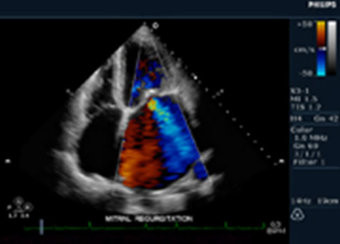

Insuficiencia mitral, dilatación auricular izquierda y valvulopatía: Insuficiencia aórtica